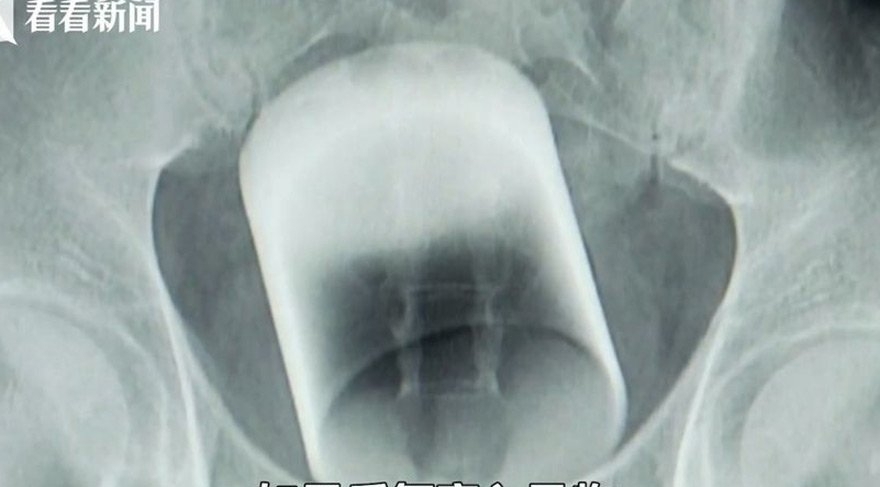

07 Eylül 2017 Perşembe 20:38Bunun üzerine ikinci yolu deneyen doktorlar ameliyat yaparak neşterle adamı kesip bardağı çıkardı. Bardağı kırılmadan çıkaran doktorlar, daha önce böyle bir durumla karşılaşmadıklarını ama hastanın sağlık durumunun iyi olduğunu duyurdu. İki gün boyunca hastanede yoğun bakımda kalan adam önceki gün kendine geldi. Çin basınına konuşan adam, bardağın kalçasına nasıl girdiğini söylemedi.